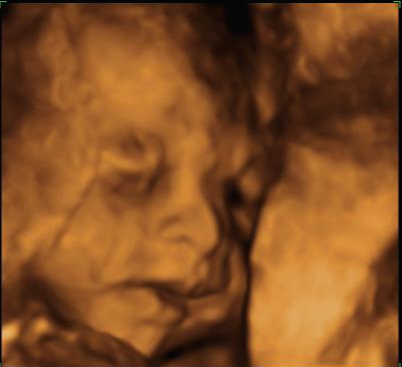

24주 차에 다시 사설로 초음파 검사를 받으러 갔는데 초음파를 보시더니 정밀 초음파 검사 때 성별 딸이 었냐 아들이 었냐 물어보시길래 딸이라고 말을 하니 미안하다고 지금 보니 딸이라고 하길래 이때는 정밀 초음파 검사 후 한 달 뒤여서 상관없다고 ㅋㅋㅋㅋㅋ 아들인지 딸인지 뭐가 중요하냐고 아이만 건강하면 된다고 하니 ㅎㅎ 그때서야 웃으시더라고요 ㅎㅎ 많이 미안했던 모양... 워낙 아이 건강상태를 꼼꼼하게 잘 봐주시고 만족할만하게 아이 얼굴 초음파 사진을 찍어주셔서 다 용서가 됐어요 ㅎㅎ

내 뱃속에 이렇게 사랑스러운 아이가 있다니 >. < 이렇게 이쁜 아이를 보면 성별반전은 중요하지 않아요~

입체 초음파 사진은 항상 만족스러워요! 사진 보면 벌써 태어난 아기처럼 어찌 이리 이목구비 뚜렷하고 아이 얼굴이 선명하게 잘 보이는지~ 제아이라 이렇게 사랑스러운 걸까요~? ㅋㅋㅋ